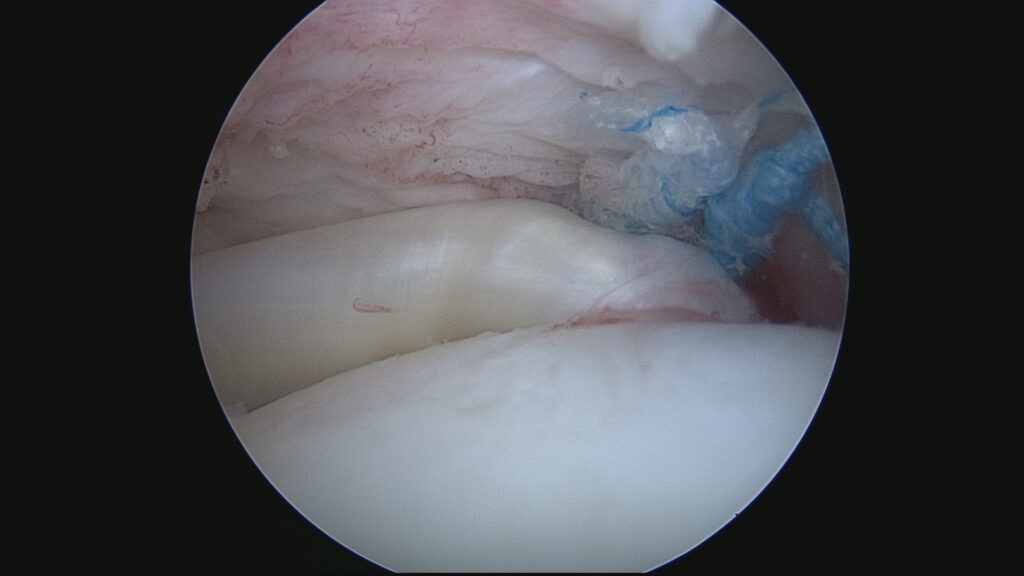

Mise en place des ancres (Vue endoarticulaire)